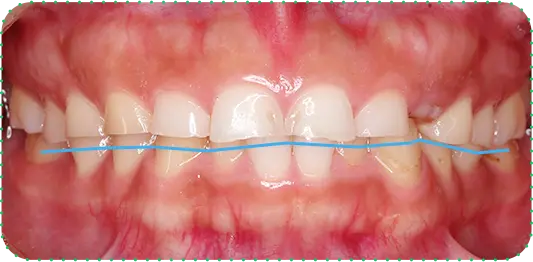

Before

After

主訴

上の前歯が長くて気になる

治療期間

9か月

治療費

30万円

治療内容

右上1番を小矯正治療にて歯茎を増やし、右上1番と左上1番をセラミッククラウンにて修復

治療のリスク

咬み合わせによっては、セラミックが欠ける可能性があります。